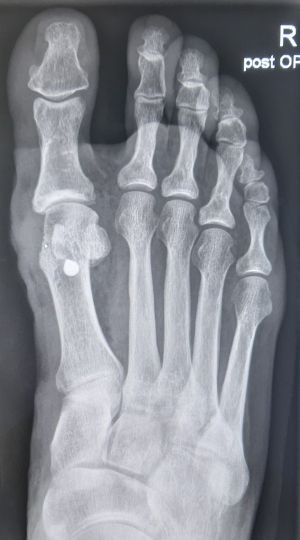

Die Diagnose erfolgt zunächst klinisch. Zur Bestimmung des Ausmaßes der Fehlstellung werden zudem Vorfußröntgen im Stehen angefertigt.

Therapie

Durch die konservative Therapie wird der ursächliche Spreizfuß mittels Einlagen behandelt. Hallux-valgus-Nachtlagerungsschienen können zu einer kurzfristigen Beschwerdeerleichterung führen, sie sind jedoch nicht geeignet, die Deformität entscheidend zu korrigieren. Bei stark ausgeprägten Beschwerden empfiehlt sich daher die Operation. Es stehen verschiedene operative Therapien zur Verfügung, abhängig vom Ausmaß der Fehlstellung, welche radiologisch durch definierte Winkel bestimmt wird. Postoperativ werden die Patienten mittels Vorfußentlastungsschuh mobilisiert.